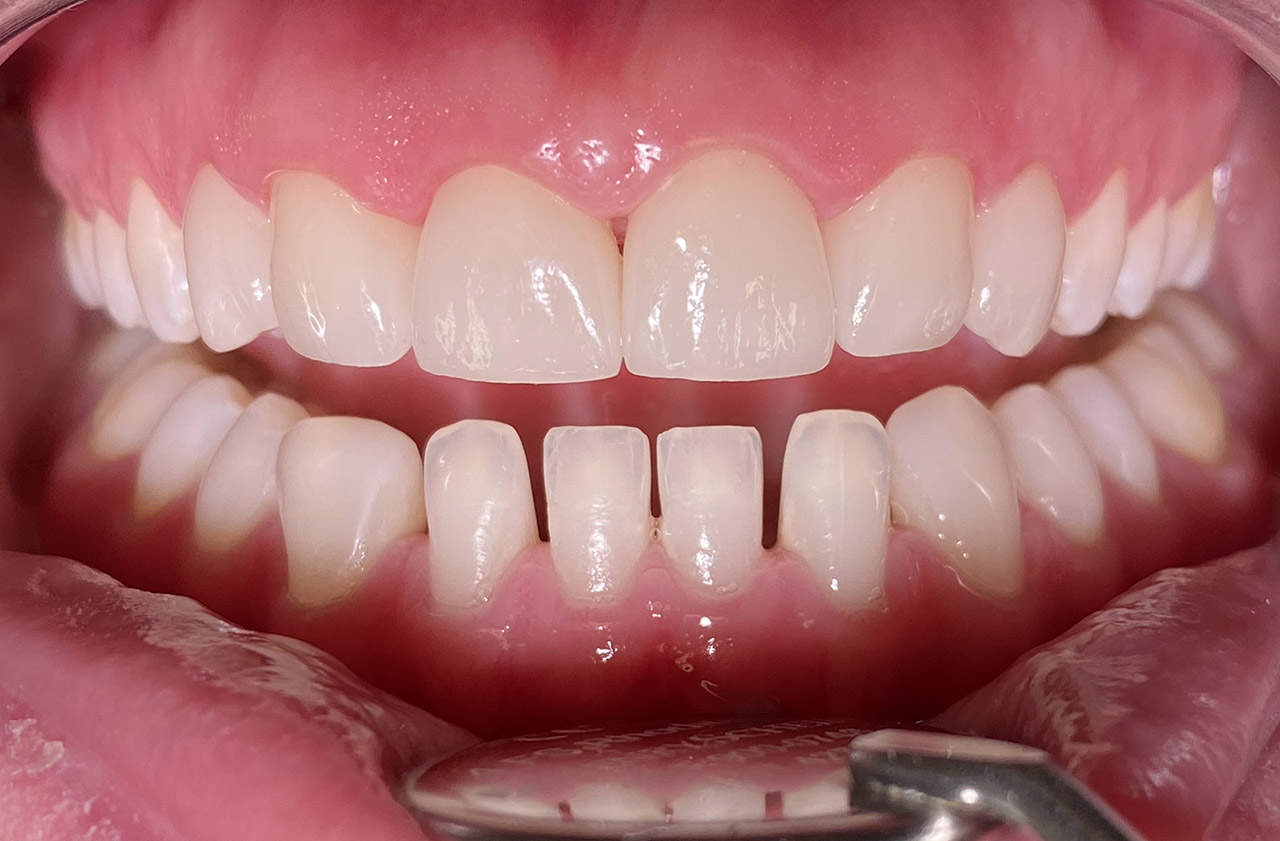

Internes und Externes Bleaching (Bleichen):

Nach Unfall mit E-Scooter unbefriedigendes Ergebnis der Erstversorgung (alio loco). Therapievorschlag: Stiftzähne?

Unsere minimalinvasive Therapie: Revision der Wurzelbehandlungen, danach internes und externes Bleaching, adhäsive Kunststoffüllungen in Schichttechnik. (Titel meiner Diplomarbeit 2003 “Die Vermeidung von Extraktion und Wurzelspitzenresektion durch zeitgemässe Endodontie in der Privatpraxis”)